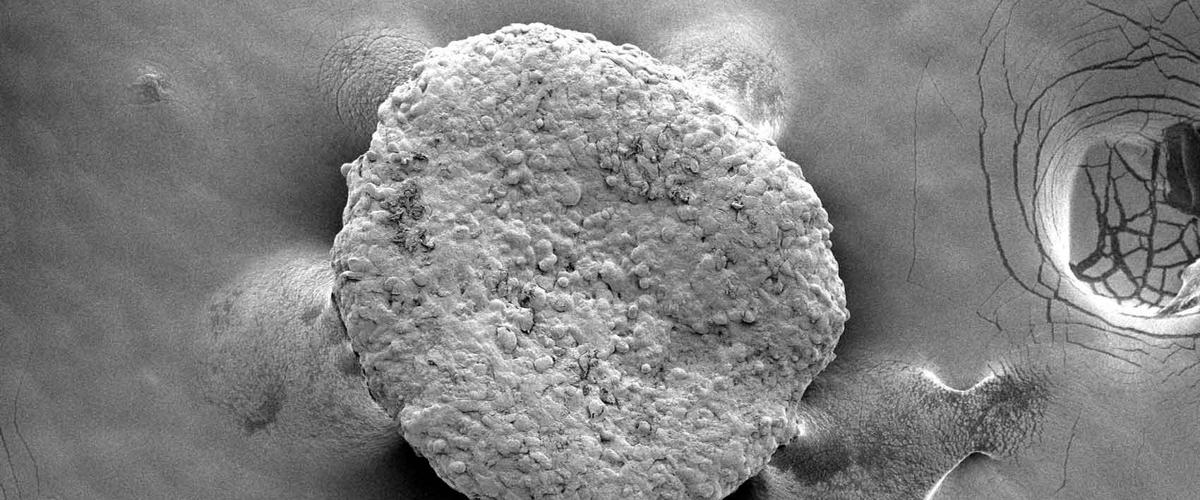

С помощью технологии генного редактирования CRISPR белые клетки превратили в бежевые, а затем имплантировали мышам рядом с опухолями. Бежевые жировые клетки очень быстро поглощали все питательные вещества, обрекая раковые клетки на голодную смерть. Примечательно, что лечение оказалось эффективным даже при имплантации клеток далеко от локализации опухоли. Это очень важный результат для будущей терапии труднодоступных опухолей, таких как глиобластома.

У мышей новое лечение полностью справилось с раком поджелудочной, простаты и груди. Удивительно, но эффект сохранился даже при условии генетической предрасположенности животного к развитию рака.